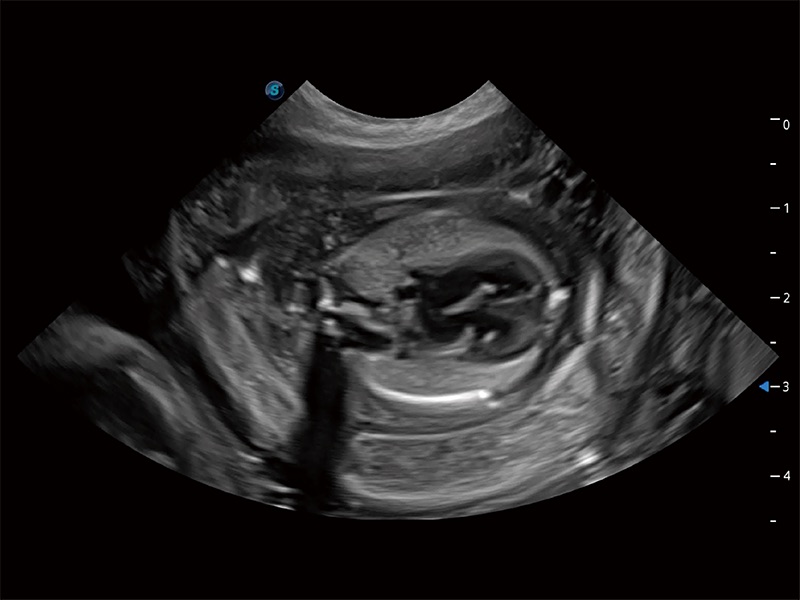

ProPet 80 全新的动物超声智能软件和丰富的探头群,为动物医生提供了高清晰度和精细分辨率的图像,无论在宠物、马科、畜牧还是实验室动物等应用中都可以轻松应对,为您的日常工作带来满意的体验。

ProPet 80 专为动物医生设计,对不同的动物体型和生理结构作出了针对性的优化。通过动物影像专用软件,可满足个性化的应用需求,帮助动物医生获得更精确的诊断数据。

高性能和先进的临床应用工具可以为动物医生提供临床信心。ProPet 80 搭载了先进的腹部和浅表应用工具,帮助医生在日常临床实践中发挥前所未有的作用。